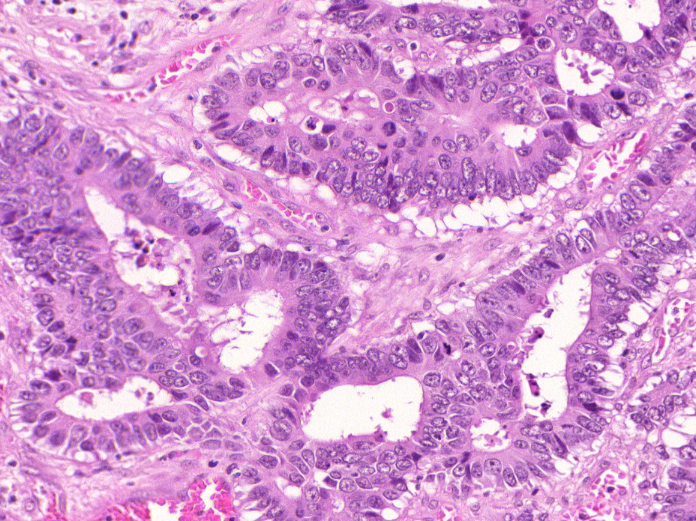

(c) GlaS Image

(f) GlaS True Mask

Figure 6: Panels (a) to (c) depict the input image for each dataset. Panels (d) to (f) represent the true mask for each dataset.

GlaS: Annotated gland segmentation images of Hematoxylin and Eosin stained slides [37].The dataset includes 165165165 manually annotated images of dimensions 522×775×35227753522\times 775\times 3, along with corresponding ground truth masks.

The Figures 6 present examples of input images along with their corresponding true masks for each dataset. The training set comprises 80%percent8080\% of the images, while the remaining 20%percent2020\% is allocated for validation. We trained our model on the training set and evaluated the estimated certainty on the validation set.